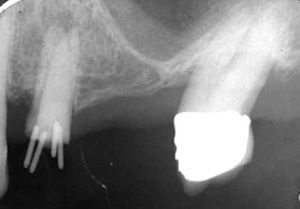

Bei diesem Fall besteht das Kauzentrum aus dem Implantat 3-i, den vier schwächsten Zähnen 21-12 und einem wurzelbehandelten Eckzahn -3. Diese beissen und kauen gegen eine Kompositbrücke mit Drahtverstärkungen (siehe hier)

Die Frakturgefahr entsteht nicht durch Bruxismus, sondern durch die geringe Grösse des Kauzentrums. Bei einem kleinen Kauzentrum werden die Zähne mechanisch gesehen gleich überlastet wie beim Bruxismus.

Nach einem Jahr ist beim Implantat +2i die Kompositfacette abgesplittert. Komposit klebt nicht an metallenen Implantat-Sekundärteilen. Deshalb wurde die Haftung mit einem zusätzlichen queren Draht und mit einem um Draht und Implantat herumgewickelten Ligaturendraht rein mechanisch verbessert.